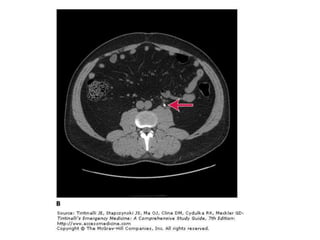

BT

• Non-kontrast helikal BT sensitif ve spesifiktir

Görüntüleme • • • • • Taşın varlığını kanıtlar Diğertanıları dışlatır komplikasyonIarı öngörür. Taşı lokalize eder Tedaviyi öngörür.

BT • Non-kontrast helikalBT sensitif ve spesifiktir